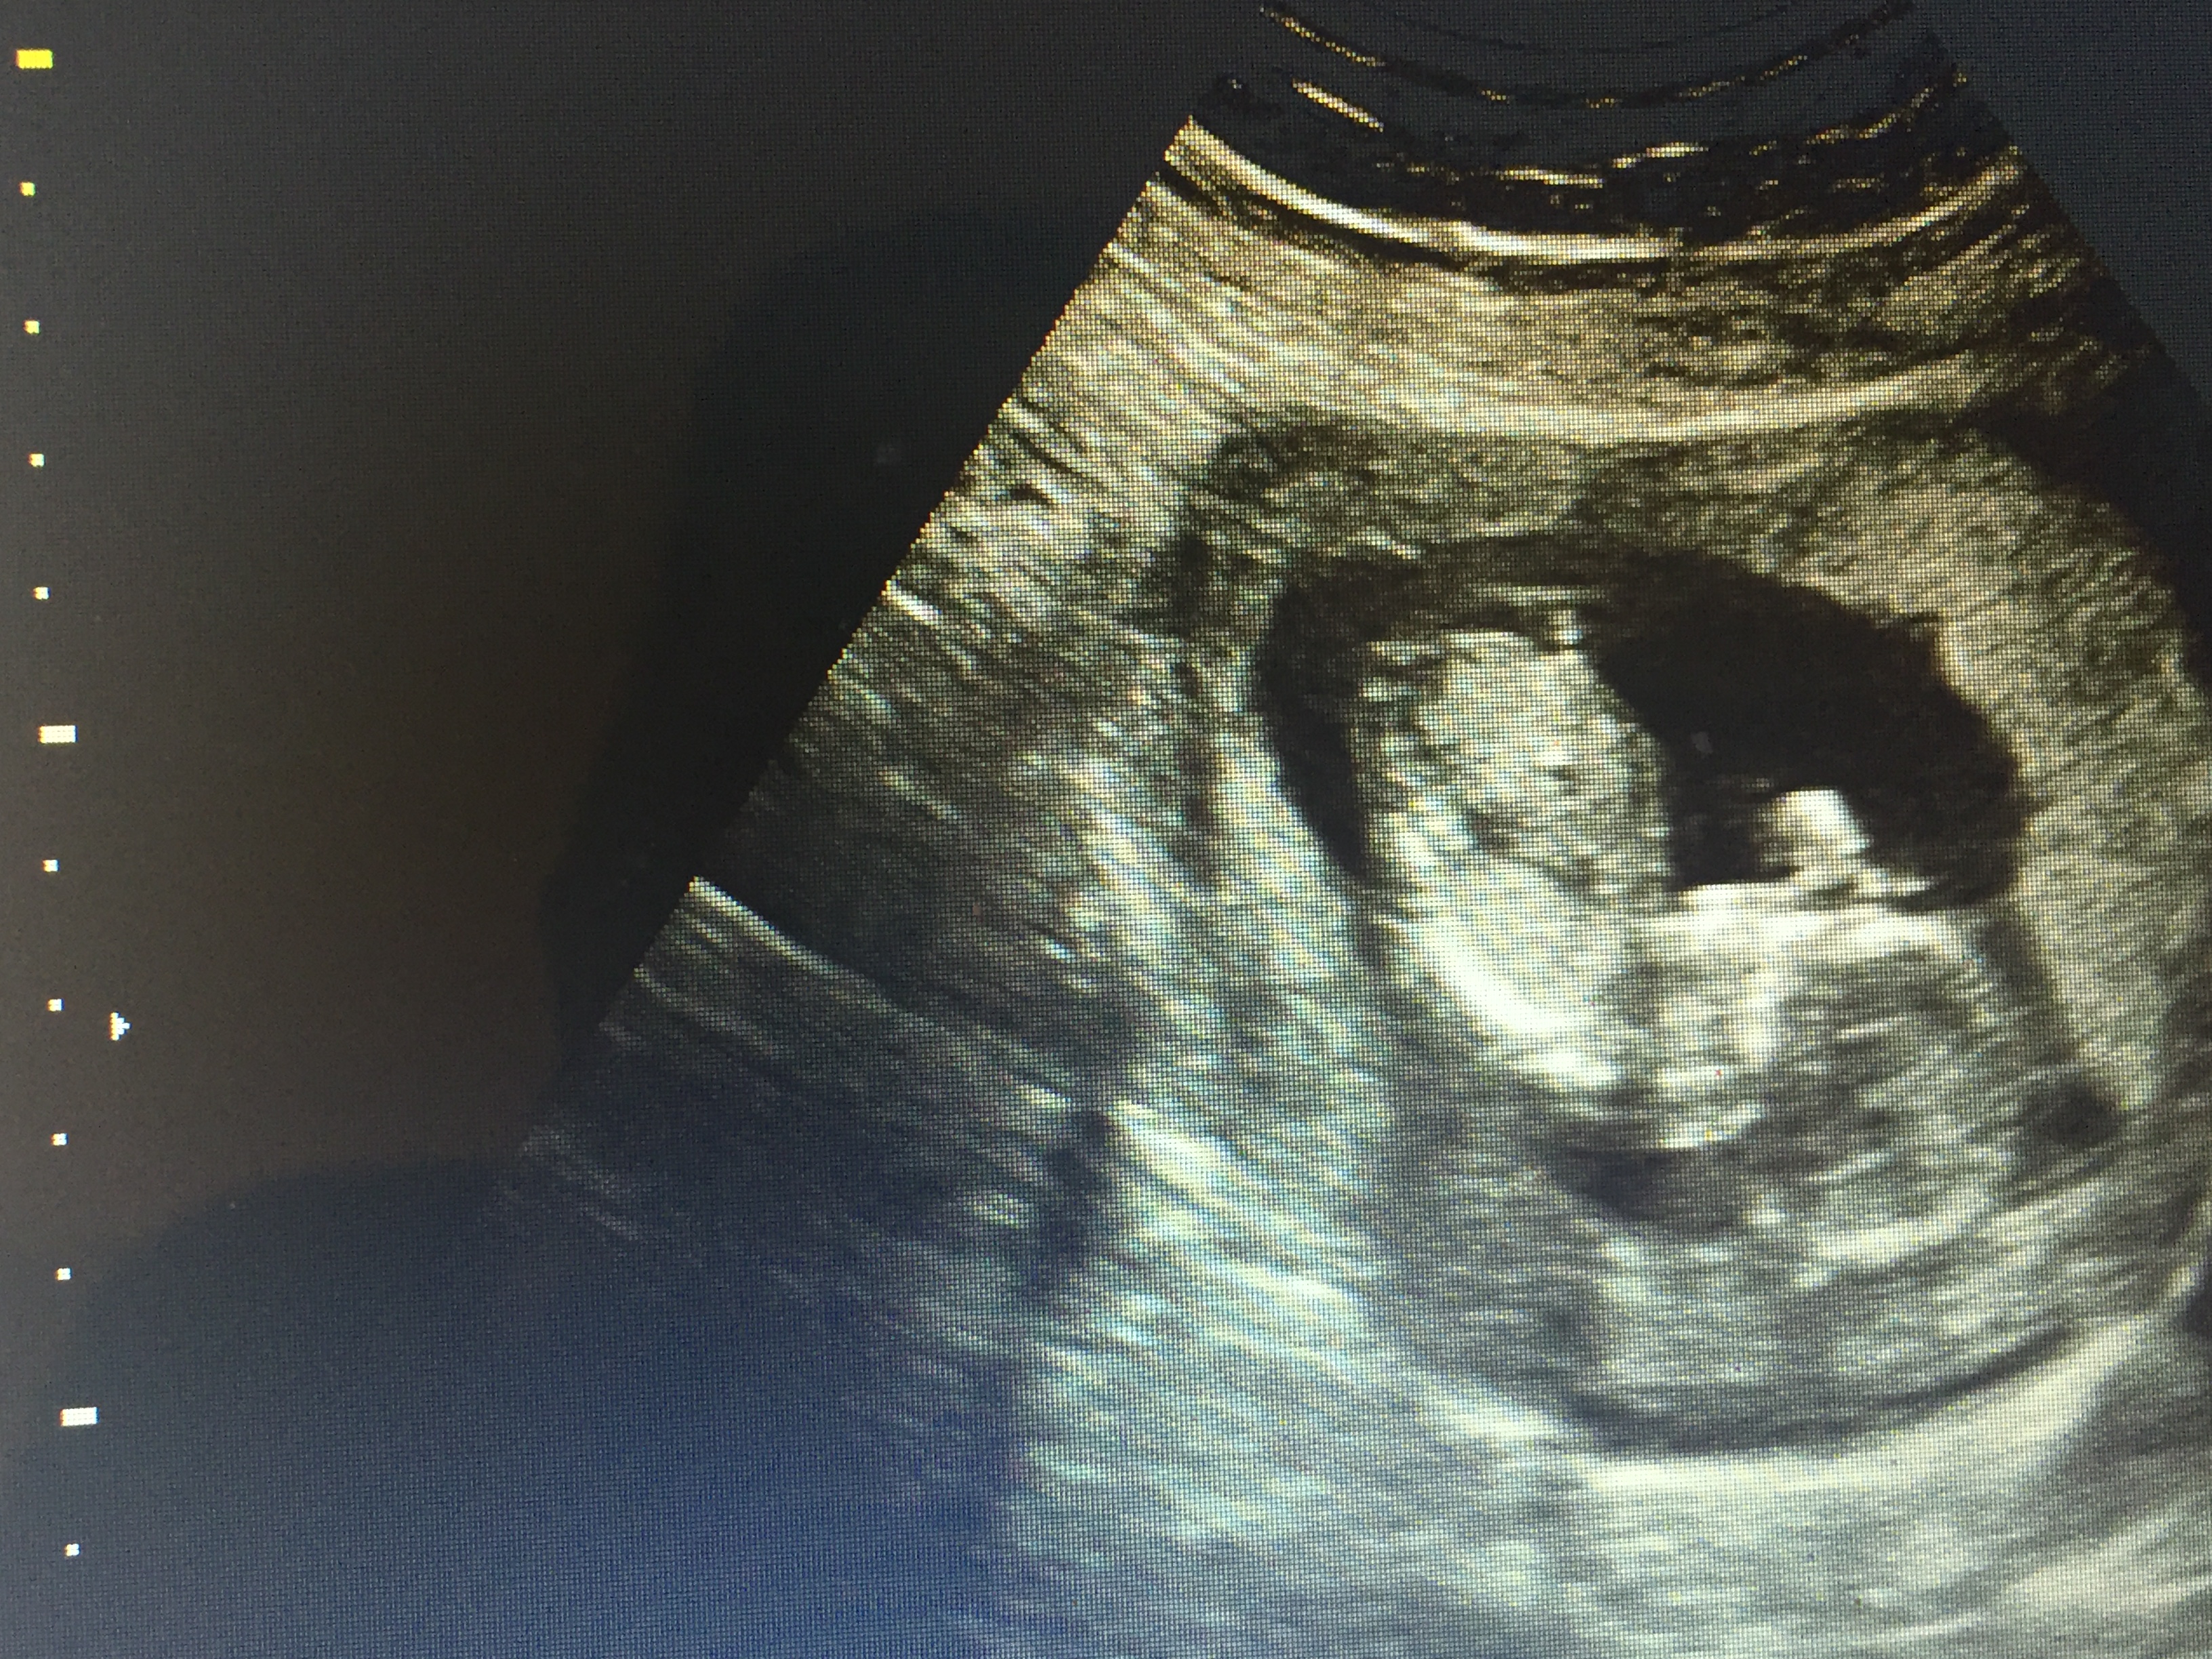

Told Boy at 13 weeks & told Girl at 16 weeks

went to an elective ultrasound at 13/14 weeks and was told boy but the Cord was between the legs and what she said was to be a "penis" seems way too long and it is also divided like a girl part. I have two boys already and their ultrasounds look completely different. After going to the elective ultrasound I saw my doctor at 16 weeksinformed us it was a girl and based off of the earlier ultrasound he gave us it looks girl also. Both my boys at 12 weeks were clear as day and this time my 13 week ultrasound from doctor had nothing between the legs.

I think the elective u/s gave us the wrong determination. Could this be a girl with swollen parts or cord over the girl parts? Attachment 28204Attachment 28205Attachment 28206Attachment 28207Attachment 28208